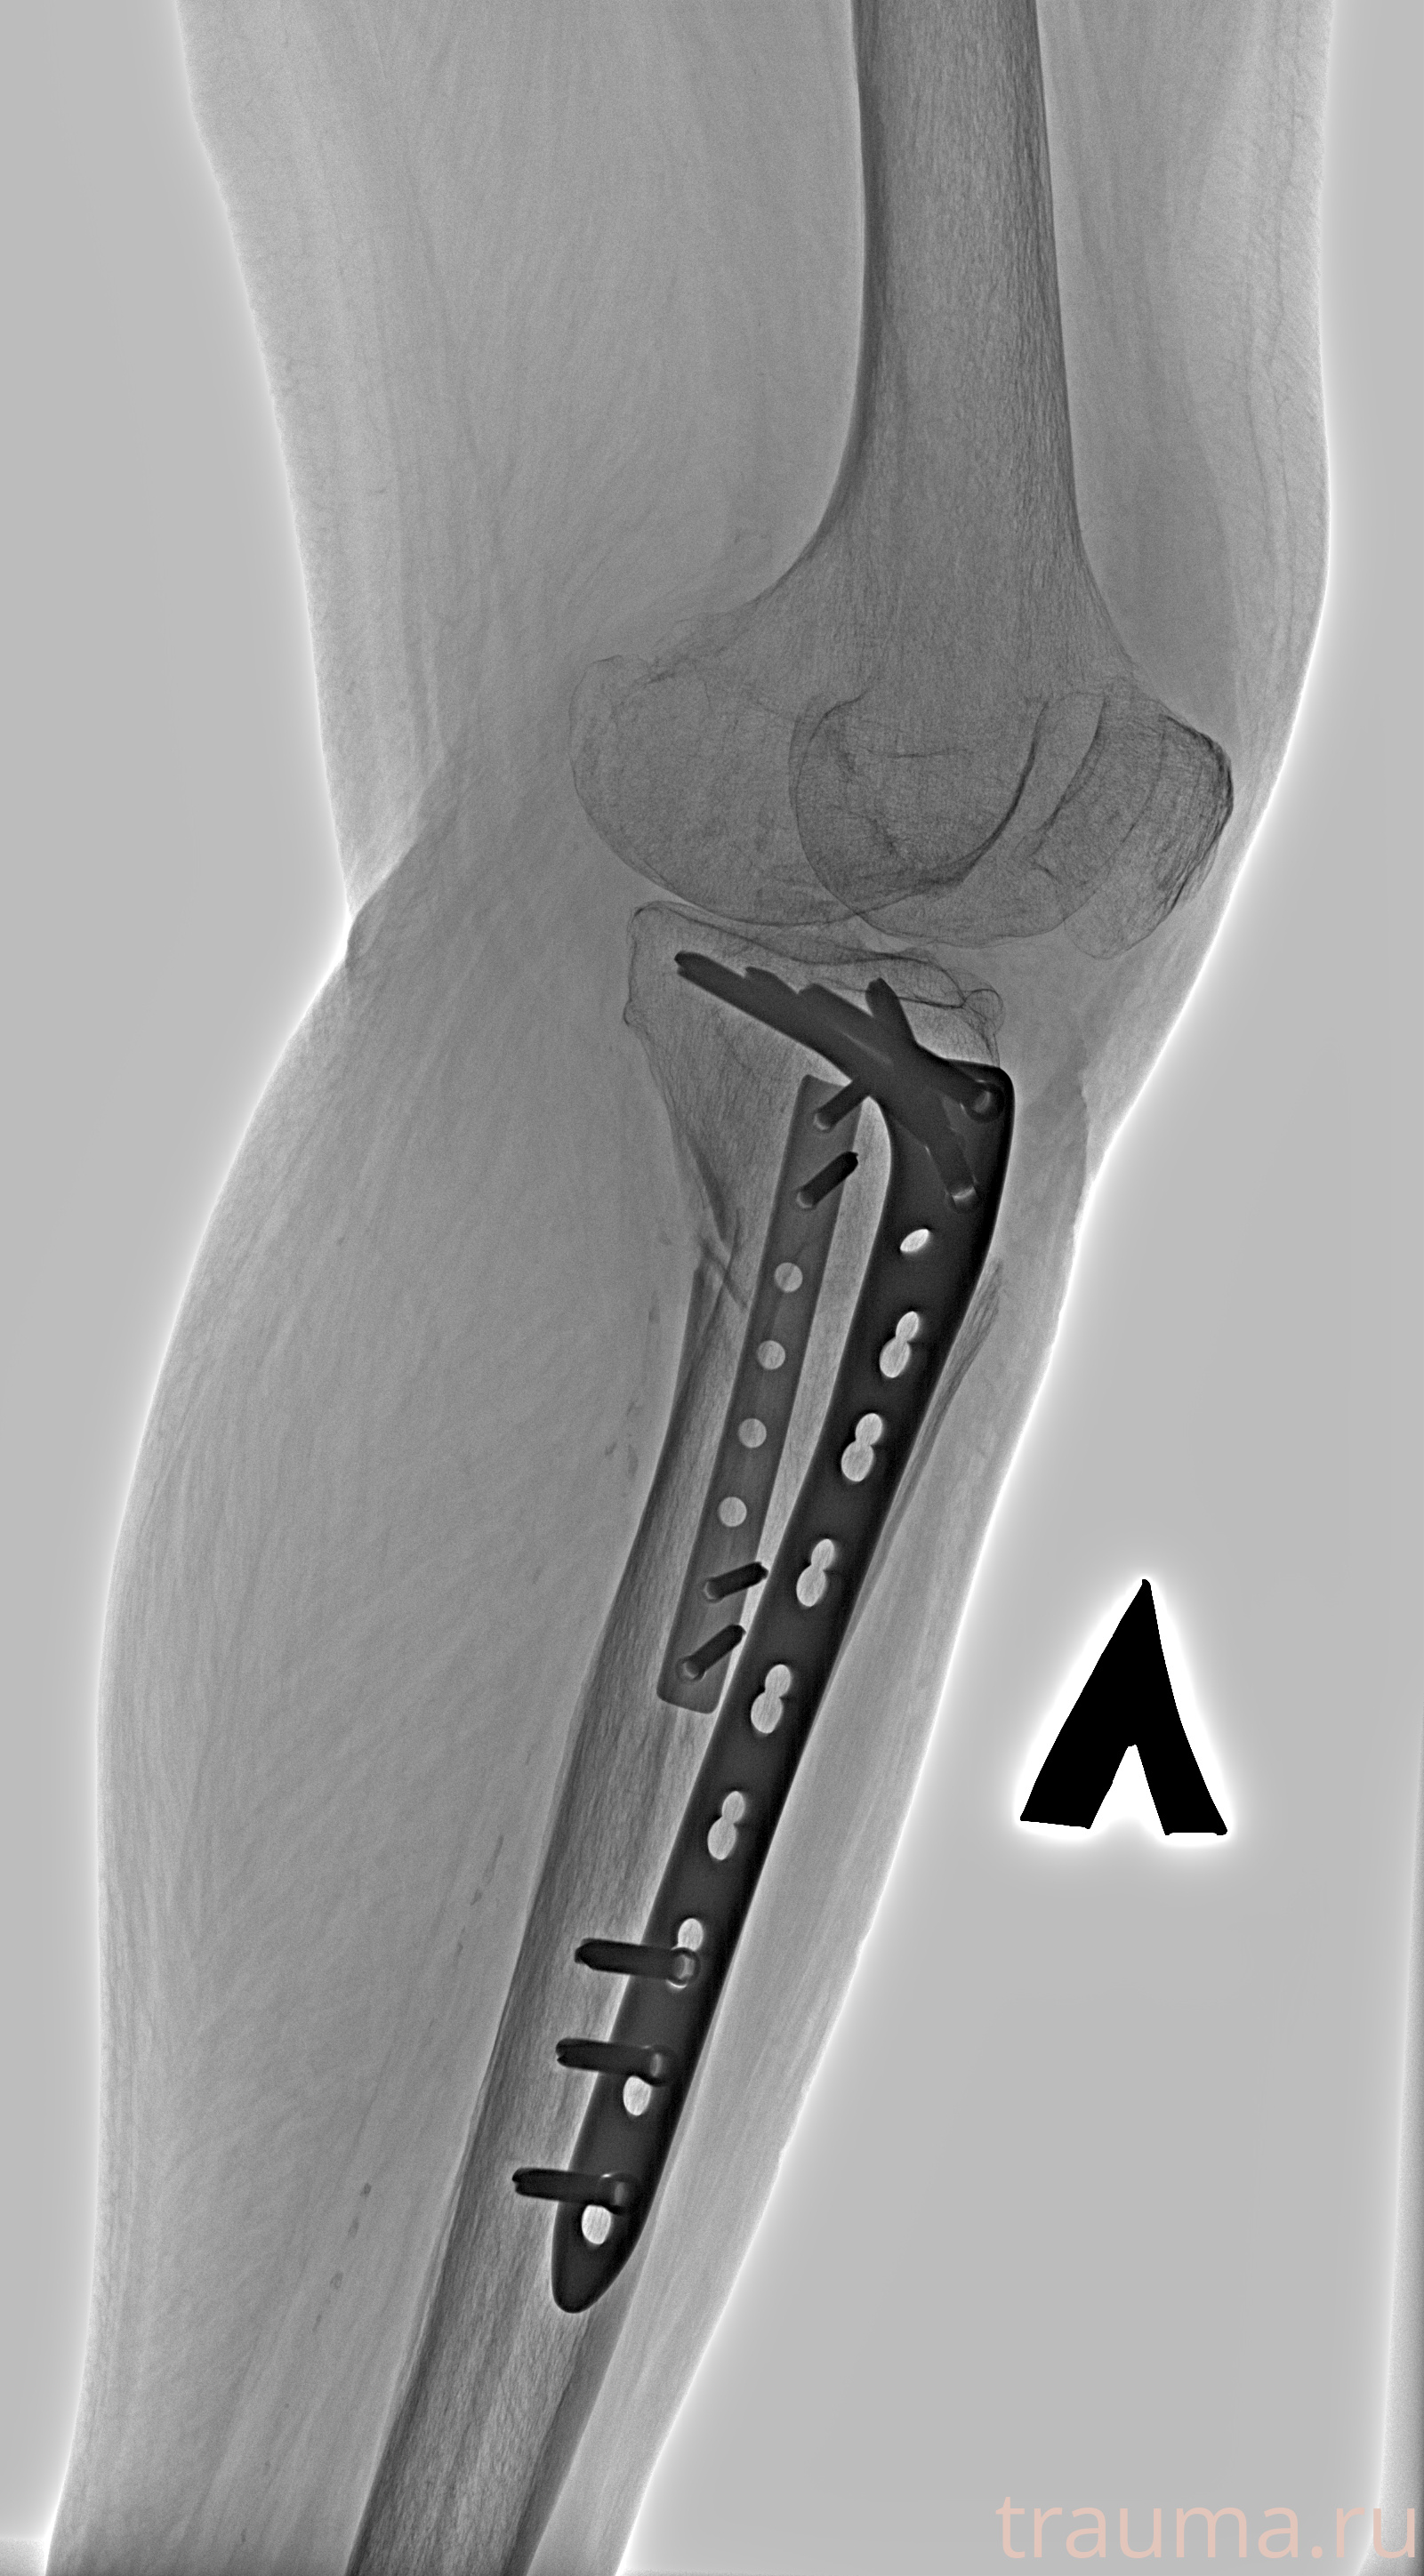

Рентгенограммы

Рентген на дому: по вашему адресу приезжает врач-рентгенолог, травматолог-ортопед с мобильным рентгеновским аппаратом, проводит диагностику травмы или заболевания, делает необходимые рентгенограммы, дает рекомендации по дальнейшему лечению. Получить качественные снимки в домашних условиях возможно благодаря уникальной методике, разработанной МосРентген Центром для института  Склифосовского